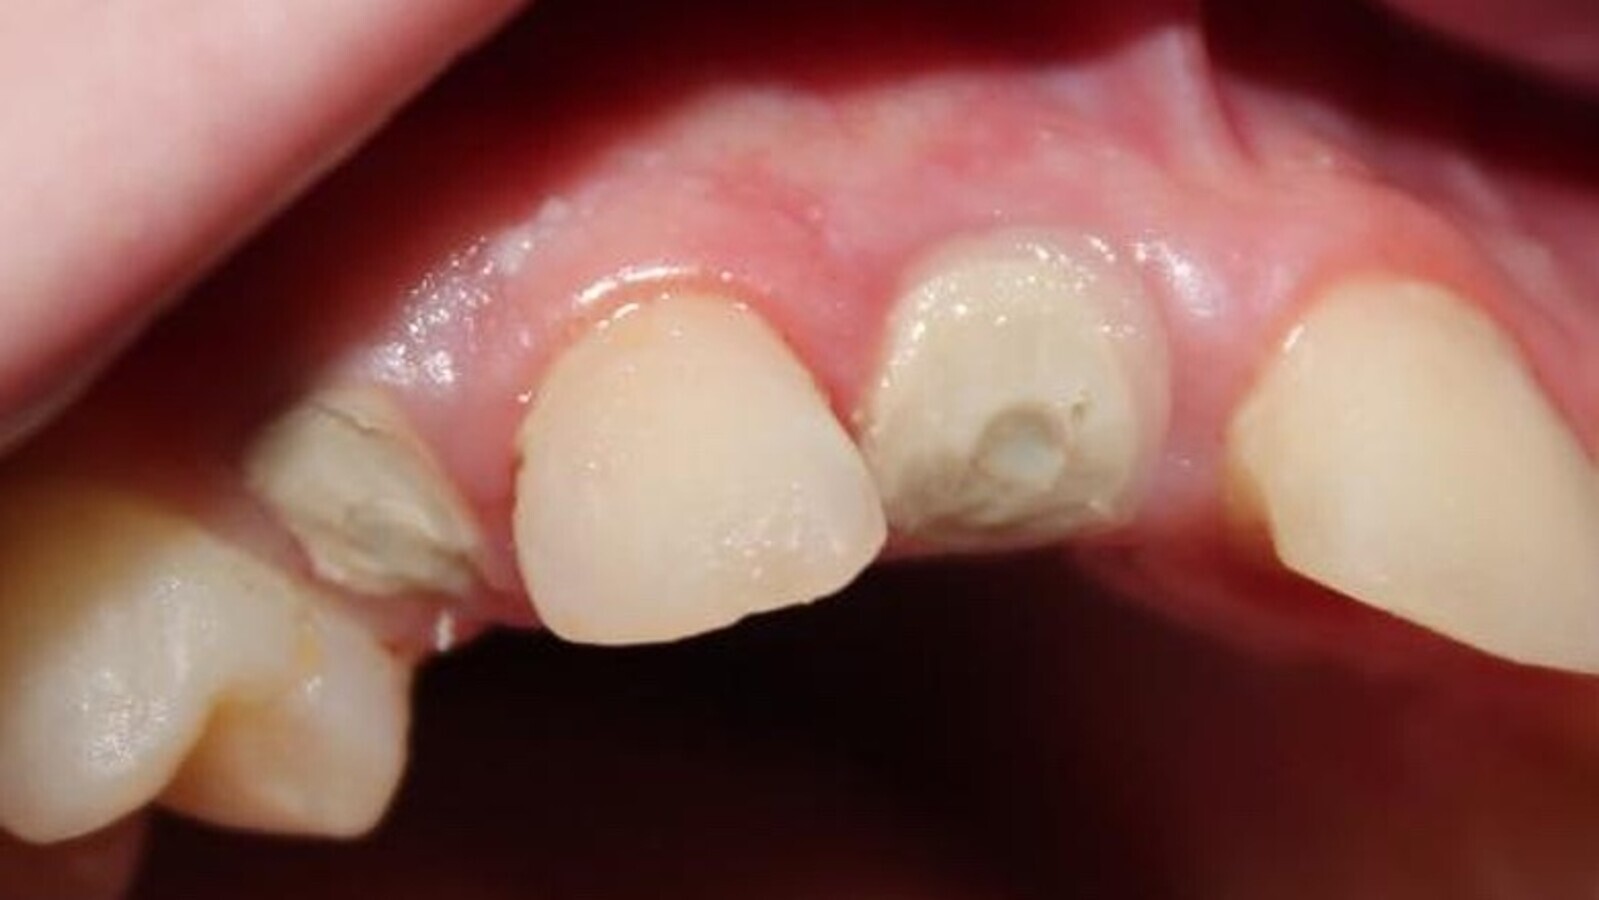

Fig. 4. Pieza 11 con desgastes proximales para la lograr exodoncia no traumática.